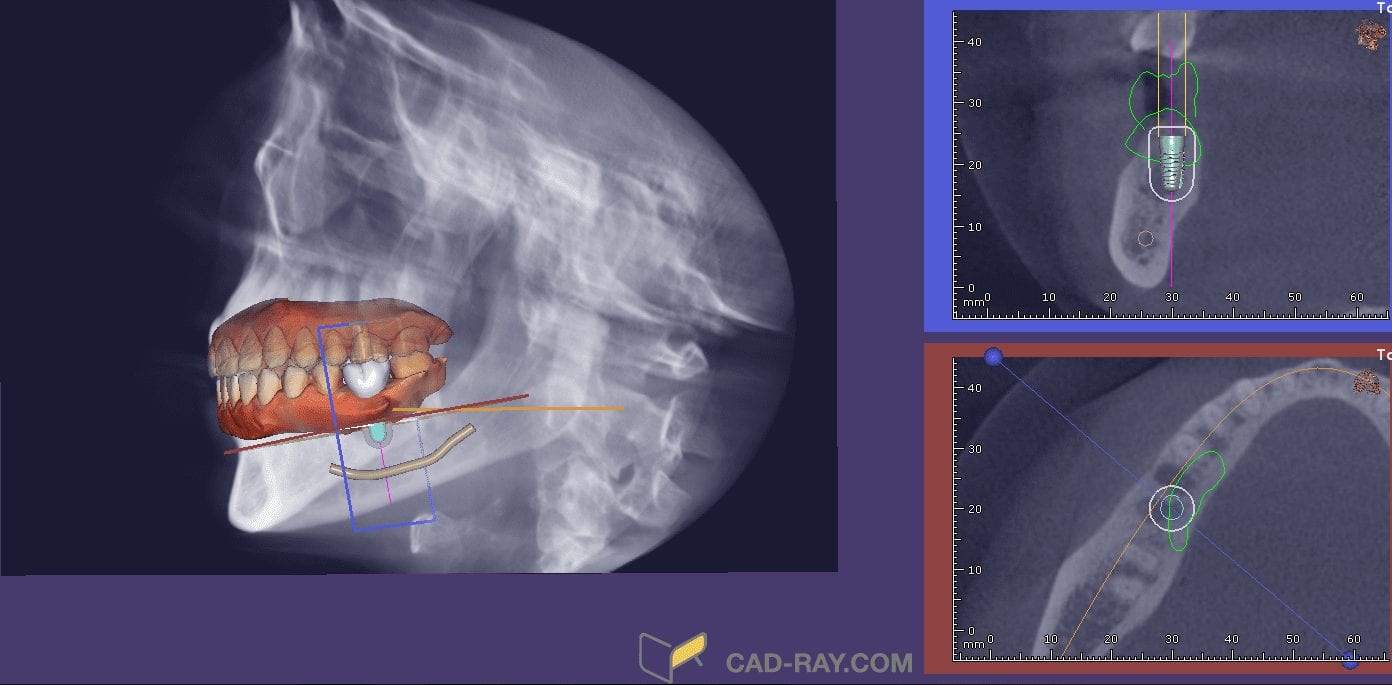

Implant Planning with Any CT Machine and Any Intra-Oral Scanner with CAD-Ray Software

February 11, 2019Our CAD-Ray software, powered by exocad and exoplan (pending 510k clearance) allows you to import your intra-oral scans and merge them with dcm files from ANY CT machine. All CBCT […]